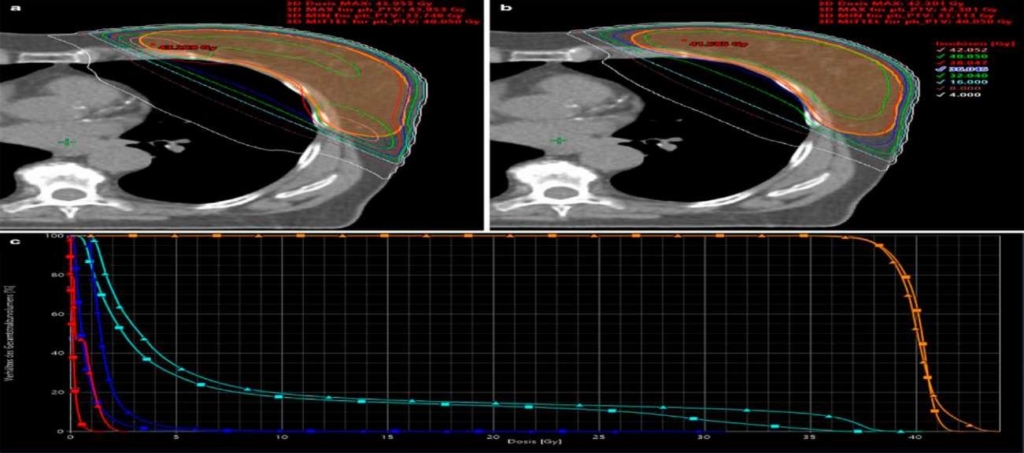

Radiotherapy involving the use of radiation to kill and shrink cancer cells has evolved dramatically over the past century and made great progress in treatment success. It has traveled a long path through different milestones resulting in fine tuning of clinical understanding, skill and technological advancement.

The overall result has been better treatment planning with improved survival and reduced side effects. Initially, superficial X- rays were developed for the treatment of cancers. With time, higher energy X-rays like Cobalt 60 were developed for successful treatment of cancers. Cobalt 60 teletherapy machines are very resilient and still in use in some African countries.

The linear accelerator was invented in the 1950’s with marked improvement in radiotherapy improving on the precision of delivery. The following are various techniques by which targeted radiation therapy is employed. These include:

3-Dimensional Conformal radiotherapy (3D CRT)- A type of radiation therapy that uses multiple beams shaped to conform to the three-dimensional outline of the tumour. This treatment targets tumours and minimizes radiation exposure to surrounding healthy tissue.

Intensity modulated radiation therapy (IMRT)- A more precise form of radiation therapy administration to precisely shape radiation beam delivery to the tumour while minimizing damage to surrounding healthy tissues.

Image-guided radiation therapy (IGRT)- A type of radiation therapy that uses imaging techniques during treatment to precisely target tumours and minimize radiation exposure to surrounding healthy tissues.

Volumetric modulated arc therapy (VMAT)-A type of radiation therapy that delivers radiation in a continuous arc as the treatment machine rotates around the patient. This allows for precise targeting of tumours.